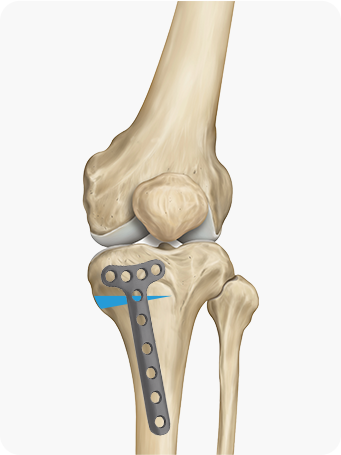

종아리뼈 일부를 절골한 후, 수술 기구를 이용하여 필요한 각도만큼 뼈를 벌려

금속판과 나사를 이용하여 고정합니다.

경골을 절골하여 원하는 각도로 벌려 무게 중심이

바깥쪽으로 옮겨지도록 교정

합니다. 절골한 부위를

금속판과 나사로 고정해 뼈가 안정적으로 붙도록 합니다.